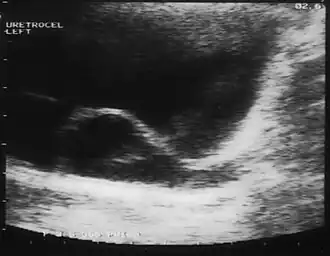

Eine Ureterozele, englisch ureterocele, ist eine kugelförmige Erweiterung eines Teils des Ureters in der Harnblase während oder nach Durchtritt durch die Blasenwand. Man unterscheidet orthotope (intravesikale) und ektope (kaudal dystope) Ureterozelen je nach Bezug zum Ostium. Eine Ureterozele ist häufig mit einer Harnleiterstenose oder einem vesikorenalen Reflux vergesellschaftet, kann aber auch symptomlos bleiben.[1]

Evtl. finden sich im Harnbefund Zeichen einer chronischen Infektion, jedoch ist das unspezifisch. Früher wurde die Diagnose im Ausscheidungsurogramm oder Miktionscystoureterogramm durch den Nachweis einer charakteristischen Aussparung im Blasenschatten und einer Erweiterung des dazugehörigen Hohlsystemes („Schlangenkopfzeichen“) gestellt. Heute beruht die Diagnose auf der Sonographie der ableitenden Harnwege mit den Leitkriterien

- randständige Zyste am Blasenbloden

- erweiterter zuführender Ureter

- Doppelanlage des Hohlsystemes einer Niere